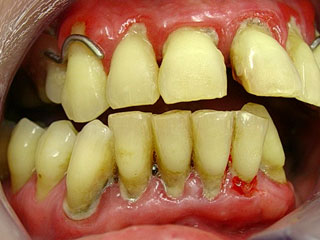

Parodontits Zahnfleischentzündung Parodontose muss schnellstens behandelt werden.

Parodontitis = akute Zahnfleischentzündung kann auch bei guter Pflege entstehen, sehr schmerzhaft und beeindruckend aber schnell heilbar ohne Verlust

Parodontose = chronische Zahnfleischentzündung mit Knochenverlust und Verlust des Zahnhaltes bei fortgeschrittenem Zustand. Muss über einen längeren Zeitraum immer wieder kontrolliert werden.

Zu spät bei Parodontose ?

Kommen Sie zum Zahnarzt auch im schlimmen Zustand, zusammen mit dem Behandler kann oft auch noch in weit fortgeschrittenen Fällen geholfen werden und die Zähne noch lange schmerzfrei erhalten bleiben. Es ist nie zu spät- schlimmstenfalls kann mit Zahnersatz und oder Zahnimplantaten geholfen werden.